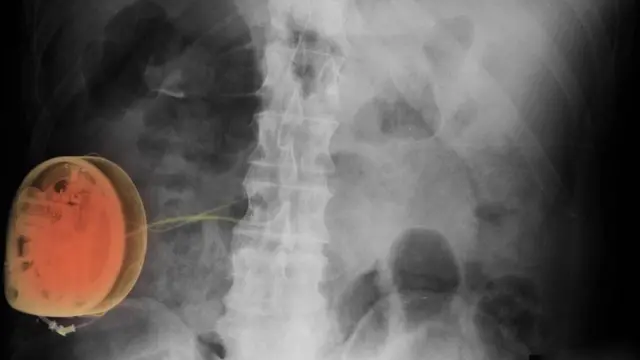

疼痛感來自於胰腺炎(pancreatitis);膽結石(gallstones)就像逃逸的罪犯,從膽囊(gall bladder)跑到胰腺裏,引起劇烈疼痛。醫生給我的妻子開了一個療程的抗生素,一個月後,妻子接受了膽囊切除手術。

一些病患來醫院時,他們身上的疼痛遠遠比背痛嚴重得多。阿爾·凱西形容了一位因患髂腹股溝神經痛(ilioinguinal neuralgia)而苦不堪言的病人——我們暫且稱這位患者為卡特吧。髂腹股溝神經痛是一種神經紊亂病症,病患會感到腹股溝有激烈的灼傷及穿刺感。

"卡特以前做過睾丸區域手術,切除了腹股溝神經。疼痛異常激烈:他來的時候,正在服用四到五種藥物,用大劑量的鴉片類藥物(opiates),還服用抗驚厥藥物(anticonvulsive medication),類鴉片類藥物(opioid patches),以及撲熱息痛和布洛芬。他的生活完全被打亂,工作難保。"備受打擊的卡特後來成為了阿爾·凱西最大的成功案例。"

鑒於飽受腹股溝疼痛折磨的卡特已經嘗試了所有治療方法,仍無好轉,阿爾·凱西就以自己的治療方法為卡特開始治療。"我們採用的是背根節刺激法(dorsal root ganglion),"阿爾·凱西說道。"這種療法會讓脊柱非常興奮,向脊髓和大腦傳輸信號。十天後,按照卡特自己的評估,疼痛降低了70%。"